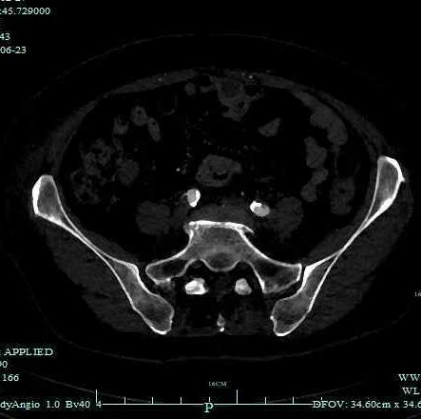

术前CTA:腹主及双侧髂动脉多处钙化病变伴管腔狭窄。

经腹主动脉造影如术中所见双侧髂动脉中-重度狭窄。

左右髂外动脉狭窄明显好转

★ 术后CTA

显示钙化病变重塑,双侧髂动脉管腔较前明显改善